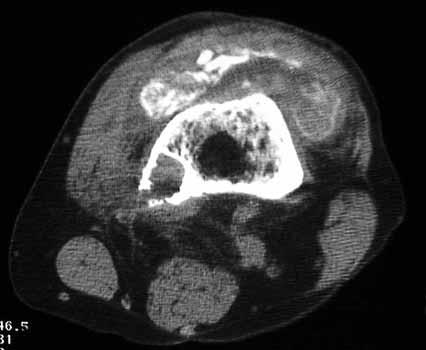

OSTEOLYSIS

Radiograph and CT

CT guided biopsy